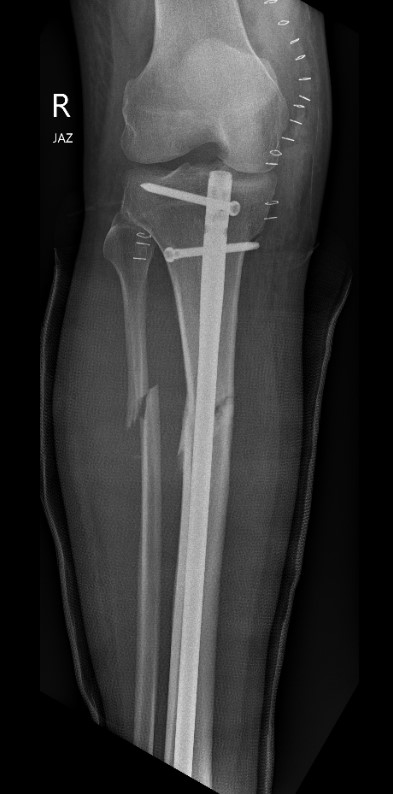

Residual proximal tibial fragment flexion - entry point too anterior

Residual valgus - entry point too medial

Reason

Standard medial and anterior entry points

- mismatch to distal canal

- canal becomes triangular

- pushes fracture into the above deformities

1. Change entry point

- match entry point to distal IM canal

- lateral in line with lateral tibial spine

- posterior